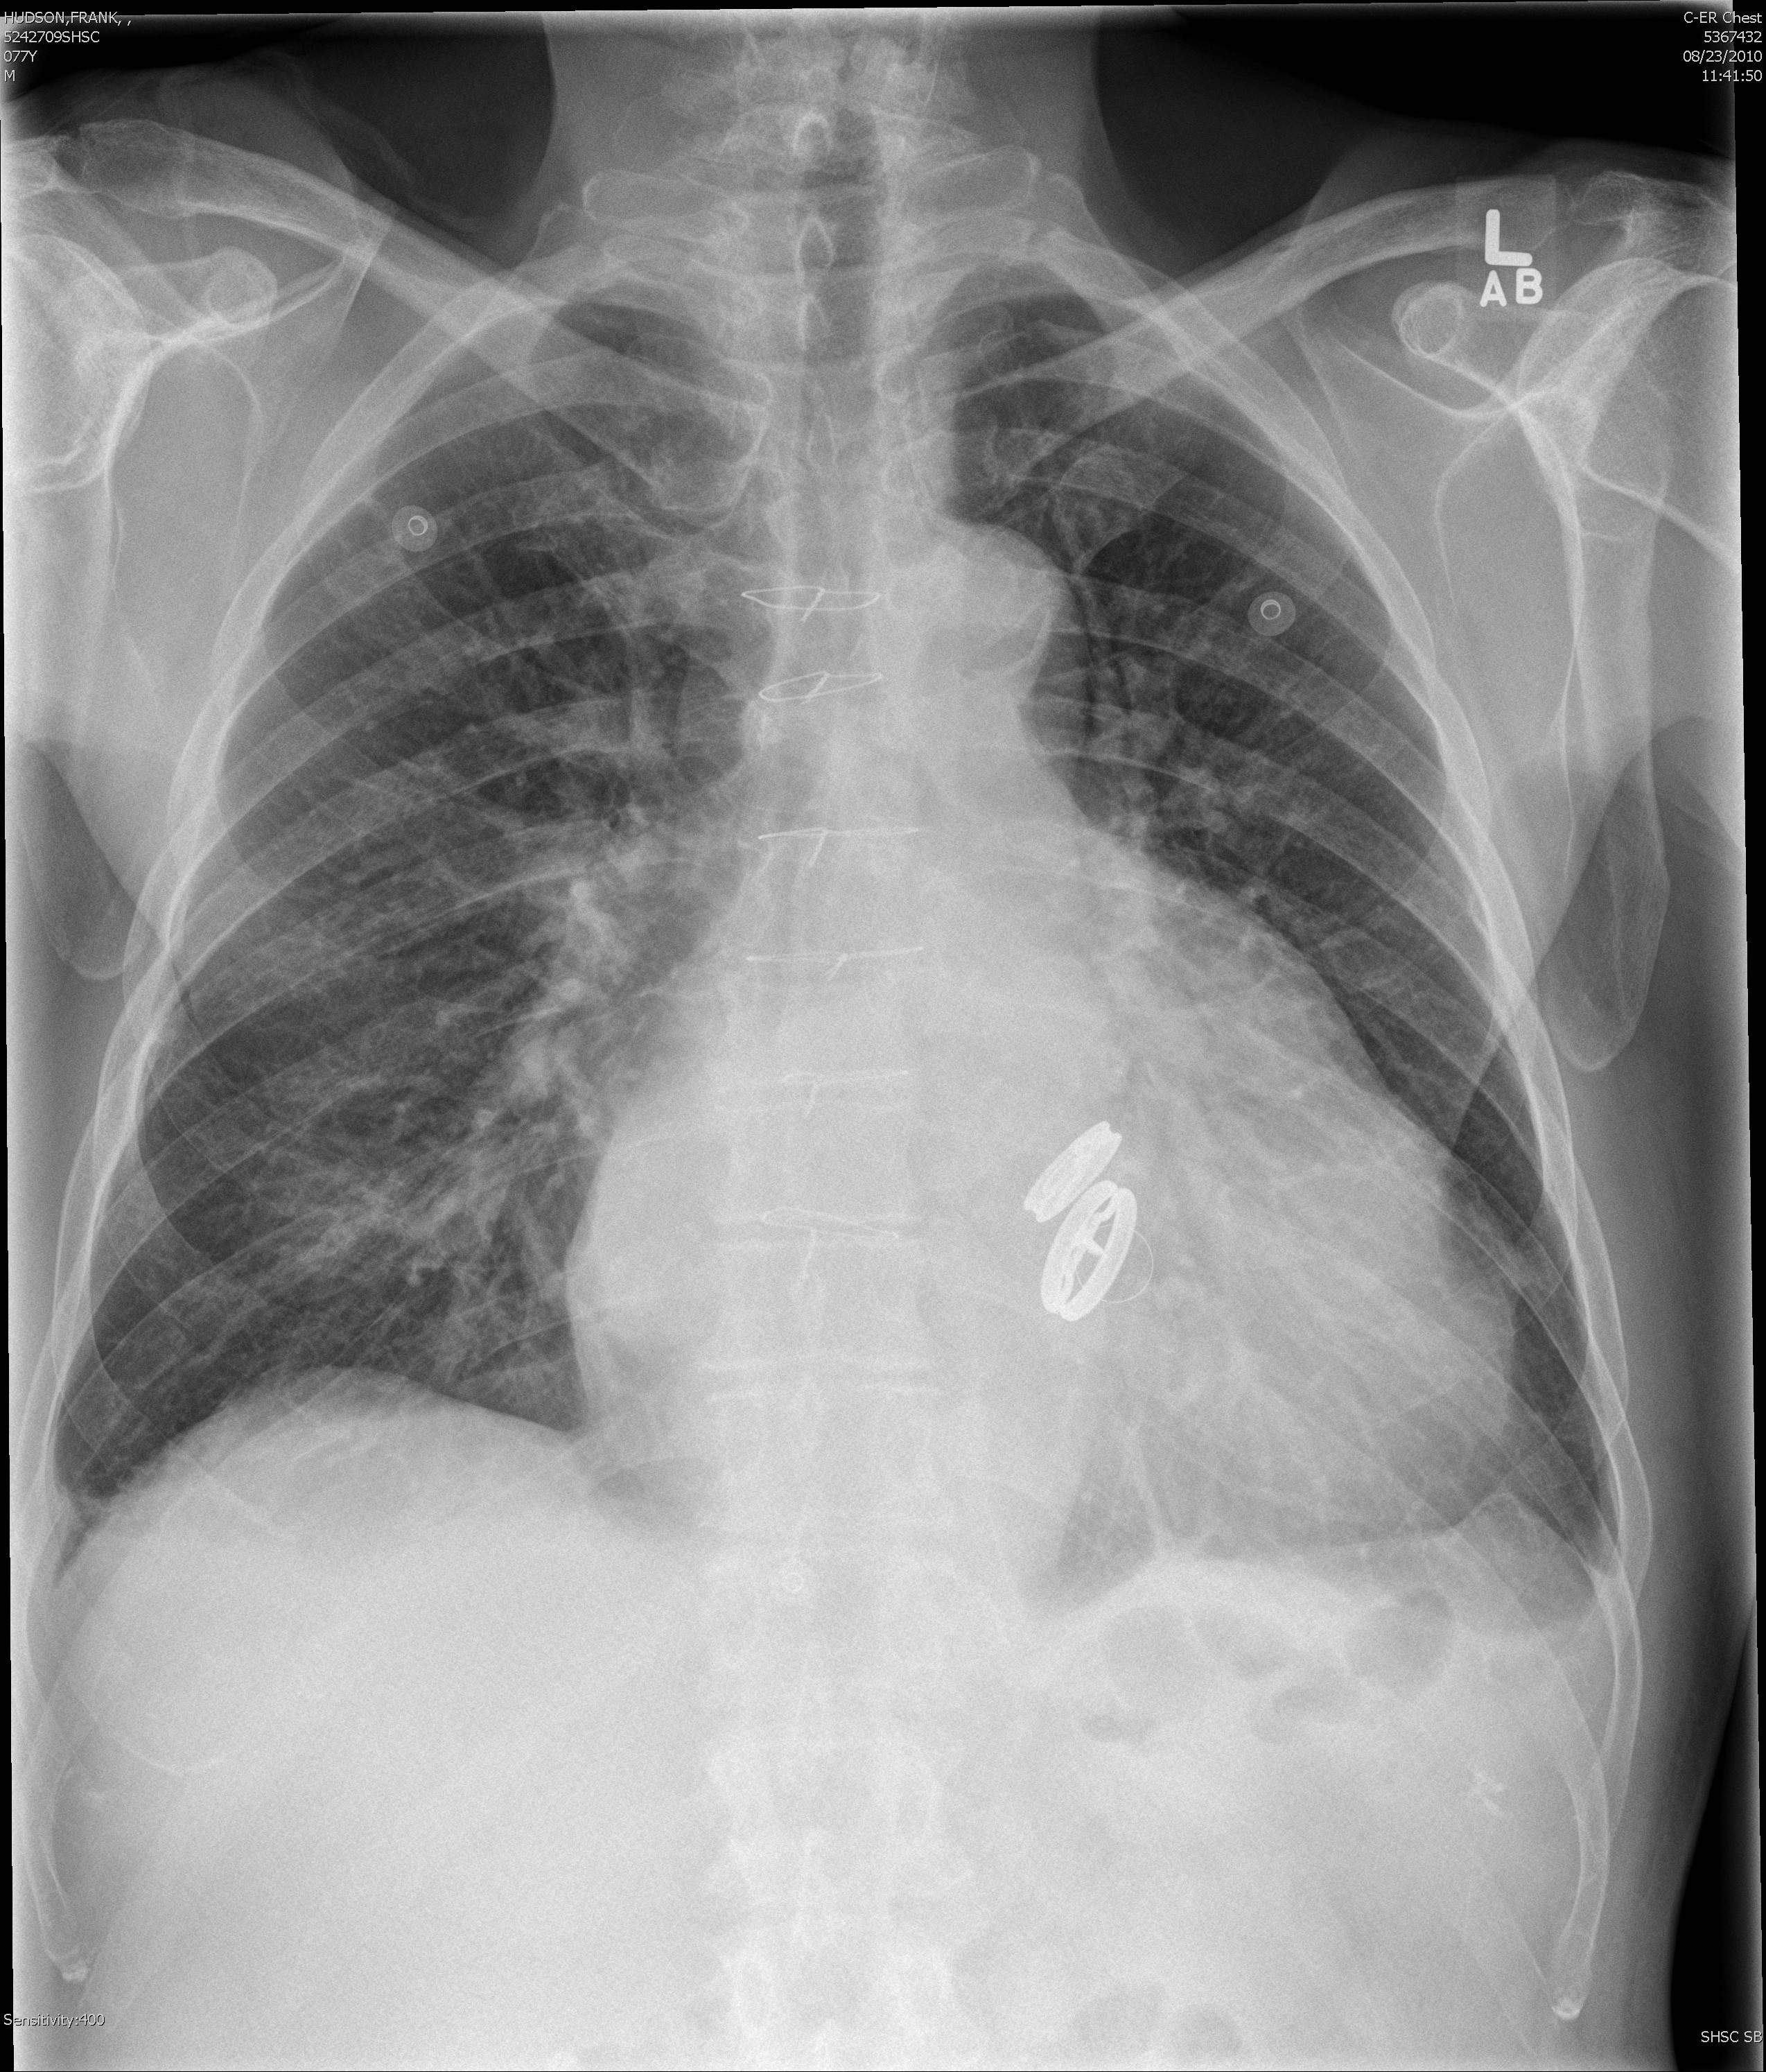

Gallery Cardiac Other prosthetic valves PA

prosthetic valves PA